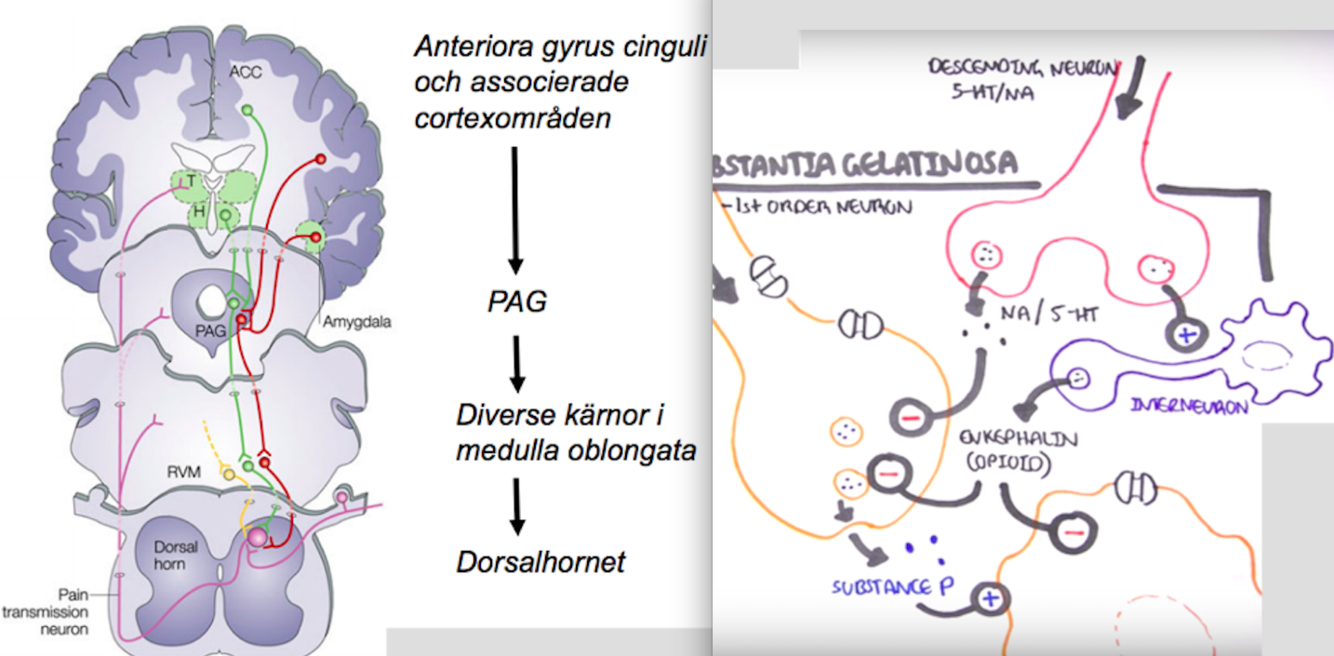

hur modulerar vi smärtan med interoception?

- Singaler ifrån anteriora gryrus och associerande cortexområden kommer gå till ett område i mellanhjärnan som heter PGA, Periaqueductal gray

- Signalen kommer sedan gå vidare till olika kärnor i medulla oblongata

- Vilka kommer sedan gå ner och inhibera synapsen mellan första och andra ordningens neroun i dorsalhornet

- Gör det via frisläppning av Noradrenalin och Serotonin som inhiberar synapsen mellan första och andra ordningens neuron.

- Frisläpper även posetiva signaler till Interneron som frisläpper Enkefaliner (sorts opioid) som hämmar första och andra ordnings neruron.